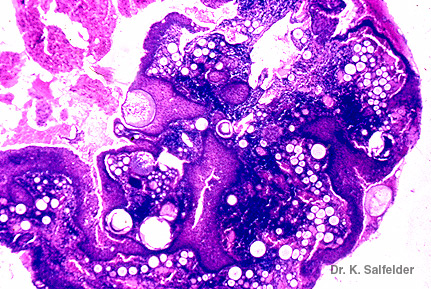

Abb. 19,6: Rhinosporidiose

Histologisches Bild bei kleiner Vergroesserung. HE-Faerbung